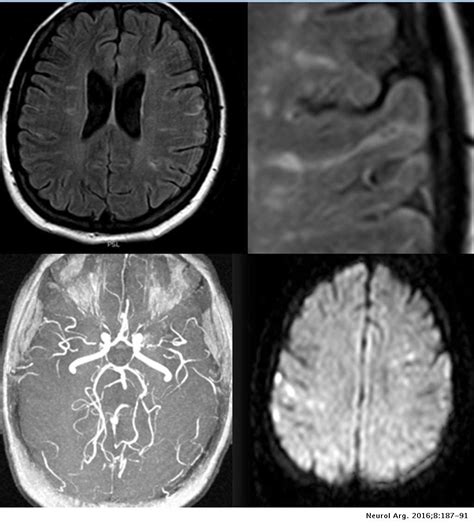

RM T2-FLAIR axial. Lesiones hiperintensas múltiples en sustancia blanca

Secuencias de Resonancia Magnética ponderadas en T2 FLAIR (a) y (b), T2

WebResumen. La presencia de múltiples imágenes puntiformes hiperintensas en la sustancia blanca (IPHSB) en las secuencias de resonancia magnética (RM) ponderadas en T2 es. Webhiperintensidades en t2 y flair puntiformes de la sustancia blanca bihemisferica y confluentes a nivel periventricular, de aspecto inespecifico. Informe de RM quisiera saber si alguien. WebHiperintensidad en secuencias T2 y tamaño como factores pronósticos de obliteración en malformaciones arteriovenosas tratadas mediante radiocirugía. Hyperintensity on T2. WebLas hiperintensidades de la substancia blanca son lesiones en este tejido cerebral que se han asociado a causantes de peligro cardiovasculares. Estas lesiones se advierten. WebUna hiperintensidad o hiperintensidad T2 es un área de alta intensidad en los tipos de imágenes por resonancia magnética (IRM) del cerebro de un ser humano. Webpresentan imágenes hiperintensas en la sustancia blanca, en estudios de resonancia magnética, cuando se observan las secuencias de T2 y FLAIR. No está claro si estas. WebEn la Resonancia Magnética se observan lesiones hiperintensas en secuencias de FLAIR y T2 he hipointensas en T1 localizadas en la sustancia blanca.